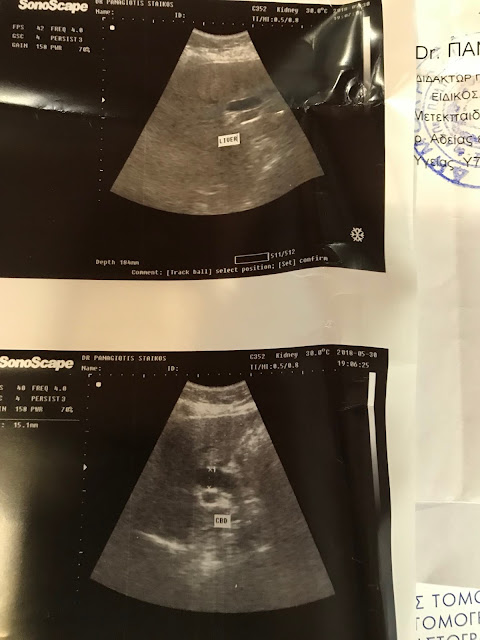

Κάνοντας όμως τον υπέρηχο διαπίστωσα , ότι είχα μεγάλη διάταση του χοληδόχου πόρου , ο οποίος  πρέπει να έχει εύρος λιγότερο από 8 χιλιοστά και είχε εύρος 15,1 χιλιοστά .